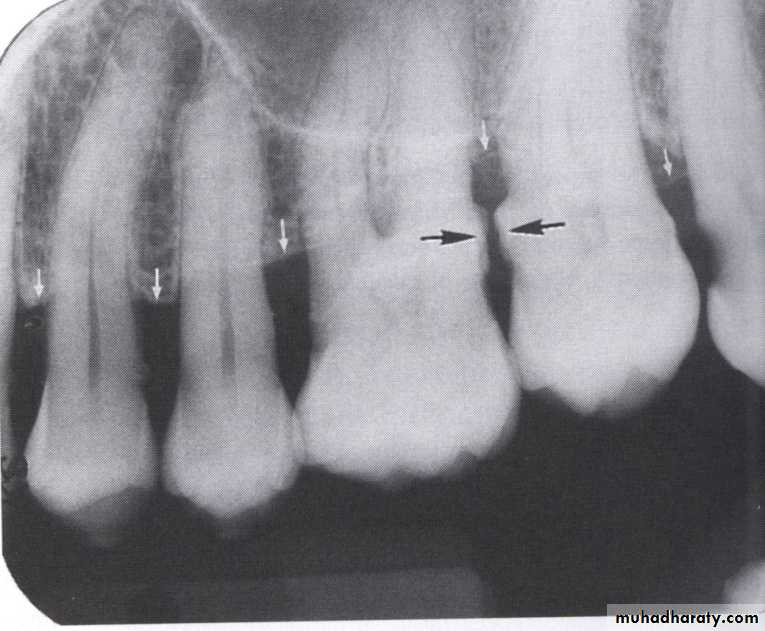

• Severity: classified to

Mild bone loss: crestal changes (The anterior regions show blunting of the alveolar crests and slight loss of alveolar bone height.Posteriorly show loss of the normally sharp angle between the lamina dura and alveolar crest).

• Moderate bone loss: bone loss of 10-33%.

• Severe bone loss: bone loss of 33% or more.

• Distribution: either localized or generalized, depend on the area involved.

• Localized bone loss occurs in the isolated area.

• Generalized type occurs evenly throughout the dental arches.